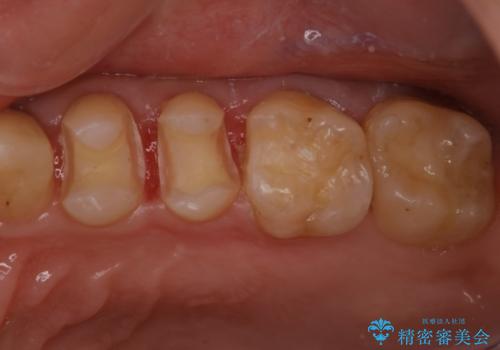

奥歯の着色が気になる セラミック治療

- 矯正終了後検査を行ったところ、以前詰めていたプラスチックの材料が着色し劣化していたこともあり、検査したところ虫歯になっていたところがあったため治療を進めることとなった。

劣化していたプラスチックをとって、虫歯をとり、形を作って、型取りをして、精度の高い詰め物(インレー)をしています。